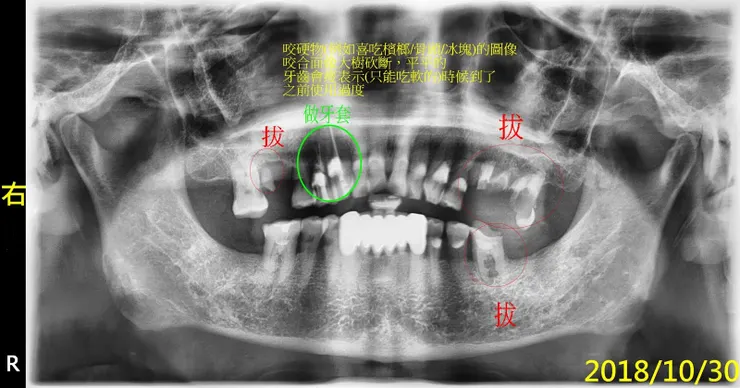

常有人好奇磨牙會怎麼磨掉牙齒?剛好有個適當的例子做說明。

接下來是比較精采,喔,不,警世的例子,說明為何我要幫每一個新病人照x光片。